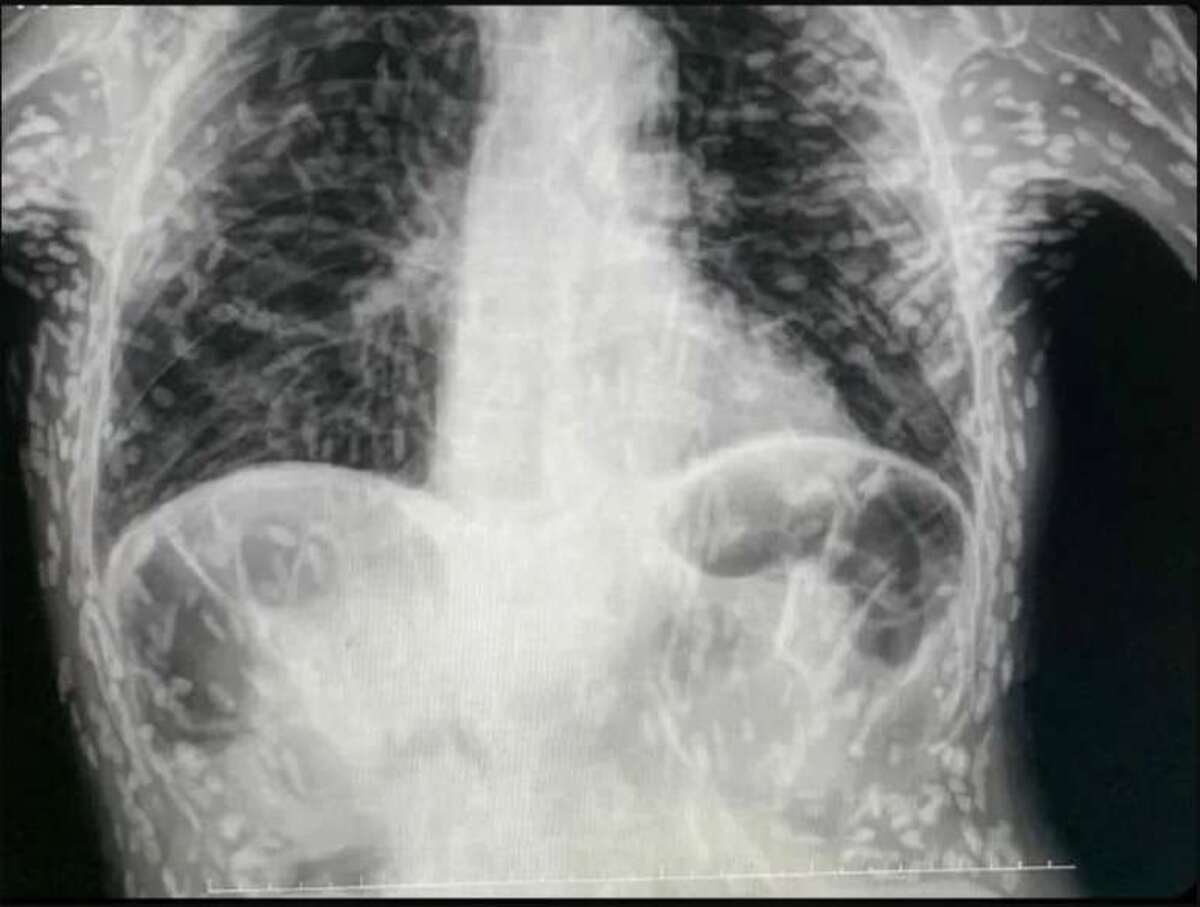

O médico Vitor Borin resolveu usar suas redes sociais para contar a história de um de seus atendimentos e acabou causando preocupação na internet. Isso porque um exame de raio-x de uma pessoa com cisticercose, doença causada pela ingestão de ovos do verme tênia, apresentava diversas marcas brancas, que eram, na verdade, larvas do parasita.

Segundo o médico, o paciente se queixava de tosse há dois meses e, por isso, solicitou uma radiografia do tórax, que mostrou a presença da tênia na região dos braços e do peitoral. A condição se chama cisticercose disseminada ou muscular e se caracteriza pela infestação das larvas em numerosos órgãos ou tecidos, sendo os mais comuns a pele, o tecido celular subcutâneo, os músculos, o cérebro e os olhos.

O médico explicou que o tratamento depende se há a presença de lesões intracranianas, medulares ou oculares. “A princípio, pacientes com cisticercose fora do sistema nervoso central e assintomáticos não precisam de tratamento”, afirmou. No caso do dono do raio-x, “as lesões estão calcificadas então não são cisticercos viáveis. Se não causar nenhum desconforto, é vida que segue”, pontuou o profissional.